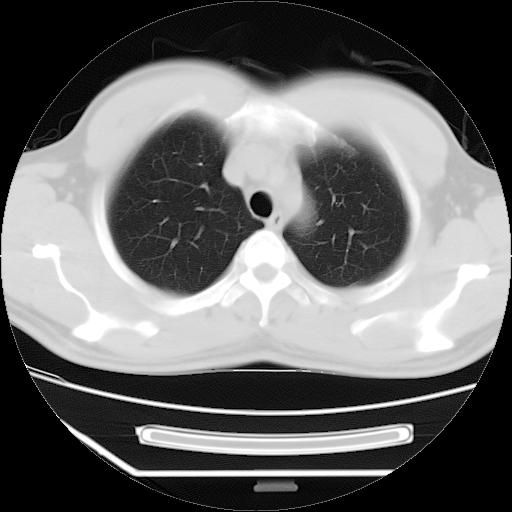

男,38岁,于2009年8月9日晚突发左侧胸痛,今x线提示左下肺阴影,为了明显确诊断,行ct检查,

病灶发生在下叶,密度均匀,边缘模糊、毛糙,周围血管纹理增强扭曲改变,靠近胸膜处病灶胸膜反应明显。

支持考虑---球形肺炎。

左肺舌叶病变。主体病灶呈类圆形中心密度低,成液化趋势周边班片影分布

考虑肺脓肿